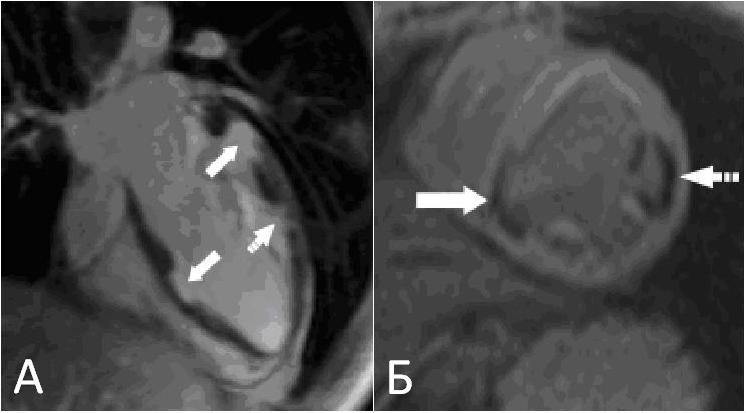

При трансторакальной эхокардиографии отмечено увеличение конечно-диастолического размера левого желудочка до 6,2 см и объёма левого предсердия до 66 мл, а также миксоматозное изменение обеих створок митрального клапана с пролапсом и регургитацией 2-й степени. Особо обращала на себя внимание выраженная неоднородность межжелудочковой перегородки с зоной локального фиброза, истончения и изменённой кинетики (акинезия, дискинезия) в средней трети (рис. 1). При компьютерной томографии сердца с контрастным усилением в 6-м и 9-м сегментах левого желудочка были визуализированы два врождённых дивертикула сердца размером 16 х 11 х 10 мм и 28 х 6 х 16 мм (рис. 2). При МРТ сердца с контрастным усилением в 6-м и 9-м сегментах левого желудочка также визуализировались врождённые дивертикулы сердца (в 6-м сегменте на всю толщину стенки левого желудочка), имевшие фиброзную стенку, с её отсроченным контрастированием. Изменения в 12-м сегменте ЛЖ были расценены как несформировавшийся дивертикул (рис. 3).